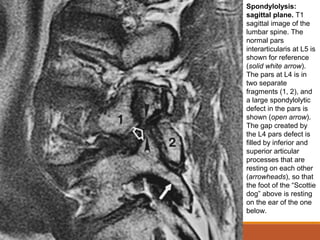

Spondylolysis:

sagittal plane. T1

sagittal image of the

lumbar spine. The

normal pars

interarticularis at L5 is

shown for reference

(solid white arrow).

The pars at L4 is in

two separate

fragments (1, 2), and

a large spondylolytic

defect in the pars is

shown (open arrow).

The gap created by

the L4 pars defect is

filled by inferior and

superior articular

processes that are

resting on each other

(arrowheads), so that

the foot of the “Scottie

dog” above is resting

on the ear of the one

below.